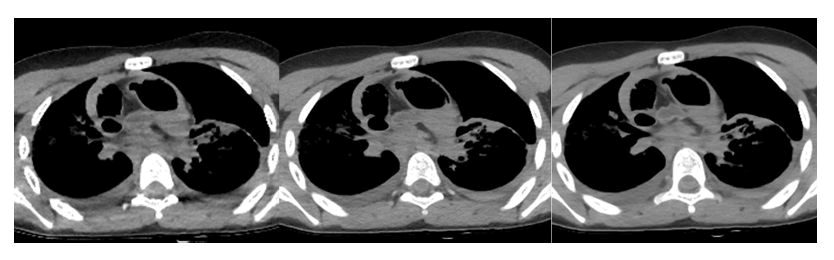

We therefore propose three sets of images where the same image is compared but extracted from three different datasets: An acquisition at 80 KV, an acquisition at 120 KV and a reconstruction using the fused CT technique of the two previous ones.

Analyzing Figure 6, which examines the mediastinal structures, it is noted that with scans at 80 KV, decent information about the anatomy of the district is obtained; Aorta, cardiac chambers, etc., are easily recognizable. However, the noise is significant and significantly affects the spatial resolution; the boundaries of the various anatomical structures can be inferred but cannot be clearly delineated.

At 120 KV, there is an increase in spatial resolution also thanks to the reduction of artifacts. Unfortunately, the image obtained is flatter than the previous one because the increase in kilovoltage results in a reduction in contrast resolution.

With fused CT, on the other hand, a seemingly flatter image is obtained compared to that obtained at 80 KV, but with a noticeable reduction in noise and the contrast resolution obtained is better than the acquisitions at 120 KV thanks to a significant increase in signal.

In the case of the mediastinum, the structure that benefits most from this reconstruction is the aorta: It is noted, in fact, how in the image on the right, the definition and visualization of the vessel wall and lumen are clearer compared to the other two images.

XXXXXXXX

Figure 6. Comparison of mediastinal images with fused CT and acquisitions at different energies: respectively 80 KV (left), 120 KV (center) and fused CT (right).